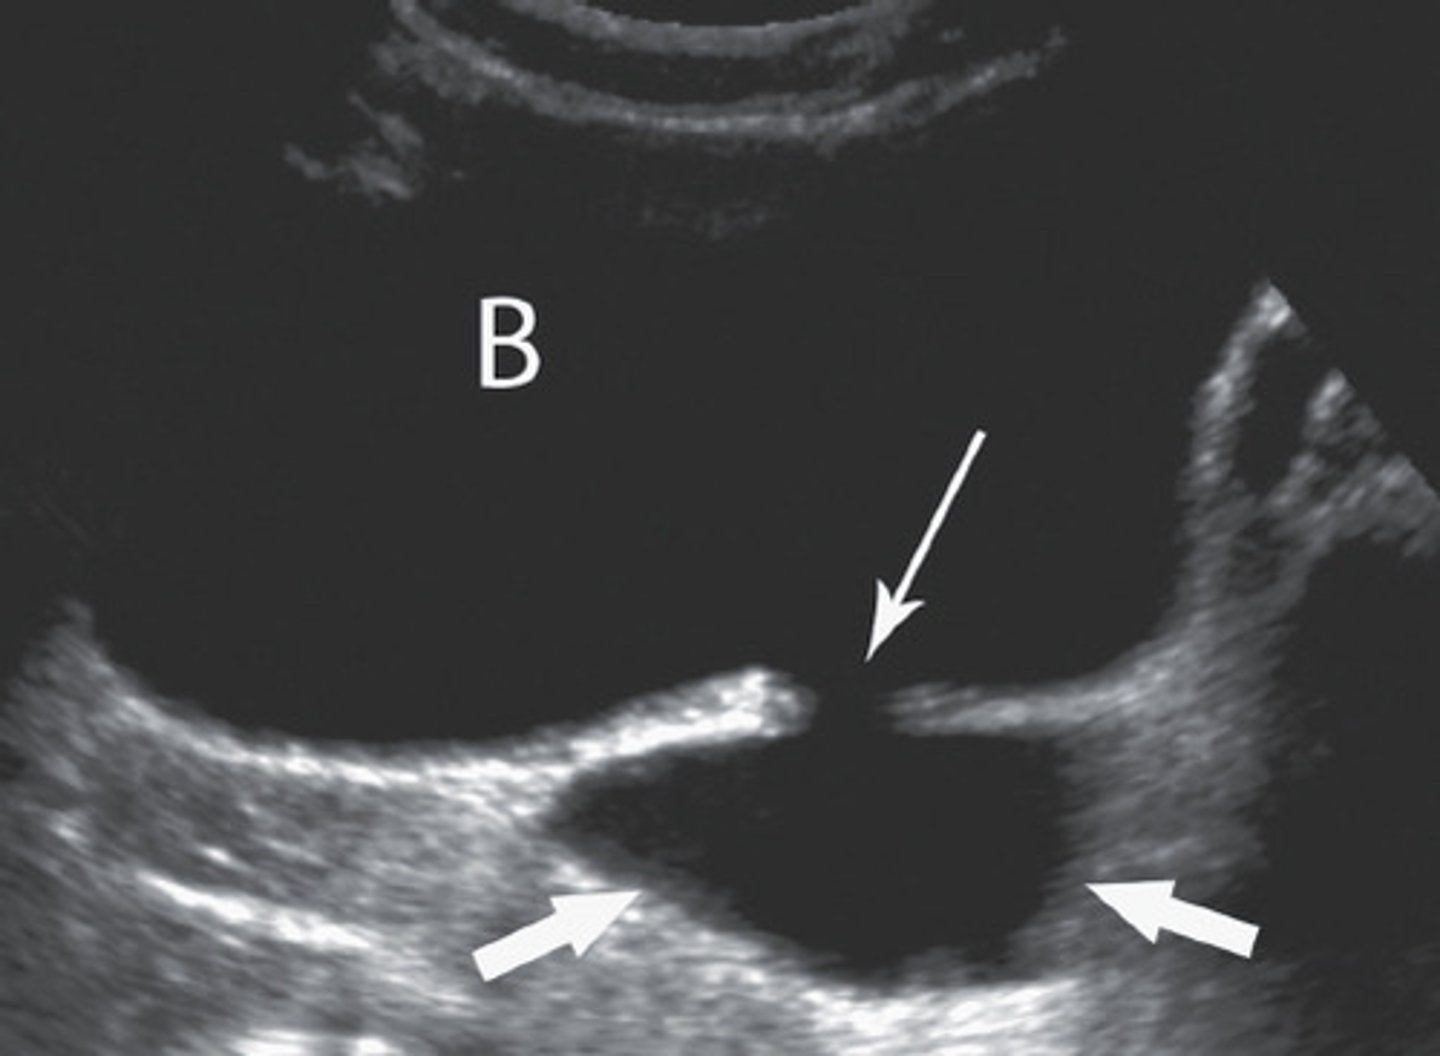

Is the bladder intra or retroperitoneal?

Sono findings of cystitis (3)

- hypoechoic wall

- focally or diffusely thickened wall

- may contain echogenic material

Chronic cystitis can lead to ___

scarring and trabeculation of bladder wall